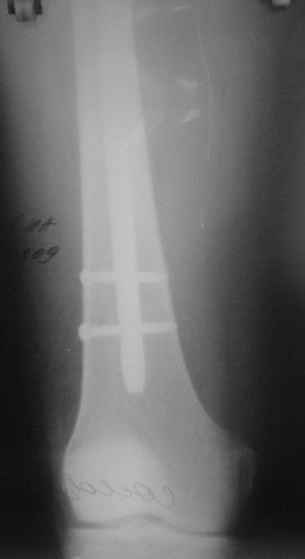

Сегодня прооперировали без открывания. Хотел-бы услышать комментарии по поводу послеоперационной нагрузки.

С уваженем, Ю.А.Булахтин

Учитывая изначальные снимки и то. что сделали , не открывая - весьма достойно. Доктор Коган прав - перелом немного перерастянут ( что хорошо видно по фибуле), а перерастянутые переломы большеберцовой срастаются очень плохо. Поэтому я бы обязательно дал раннюю динамизацию - на 6 неделях ( когда можно не опасаться малротации) разблокировал бы проксимальный фрагмент полностью и начал бы нагружать ногу. Будьте готовы к остеотомии ( или остеоэктомии участка) малоберцовой чеерз несколько месяцев- уж слишком хорошо стоит - очень вероятно, что срастется рано и будет держать большеберцовую перерастянутой

вдогонку - до разблокирования нагружать противопоказано - все, чего добьетесь - погнете шурупы. причем, если погнете дистальные ( как обычно бывает) - гвоздь провалится в сустав. Нагружайте птолько после проксимальной динамизации, когда будете уверены, что гвоздь поднагрузкой будет смещаться вверх, а не вниз

По представленым снимкам, "контакт" между отломками не очень =(. А боковой проекции нет?

Если "так оставлять", то время начала нагрузки мало повлияет на результат.

Уважаемый Юрий Алексеевич, сложный перелом, смелое решение, хорошее исполнение и, надо надеяться, хороший будет результат. Но, что бы он (результат) был достойным, надо подготовиться и к худшему. В чём, с моей точки зрения, главная проблема, которую придётся решать. Да, вне всякого сомнения, система нуждается в ранней динамизации в совокупности с ранней же нагрузкой. В данном случае, мне кажется, можно было бы решиться и на первичную динамизацию, то есть проксимально блокировать гвоздь только через овальное отверстие, отказавшись от введения винта через круглое отверстие. В этом случае и нагрузку можно было бы начать раньше, чем через 6 недель, не опасаясь перелома дистальных винтов. Однако, имеющееся лёгкое вальгусное смещение может прогрессировать в случае полной нагрузки, которую, как справедливо отмечено форумом, требует имеющееся стояние отломков. И предотвратить дальнейшее вальгирование может достаточная наружная опора, которая возможна при хорошем стоянии поперечного перелома малоберцовой кости даже без его внутренней фиксации, как раз как в представленном случае. А, в то же самое время, раннее сращение малоберцовой кости может препятствовать консолидации большеберцовой кости. То есть, своеобразный замкнутый круг может получиться. И так, главная проблема, с которой мы можем здесь столкнуться зависит не от диастаза между основными фрагментами, и не от вальгуса, и не от хорошей репозиции поперечного перелома малоберцовой кости - а от совокупности всех трёх факторов.

Поэтому, мне кажется, пациент будет требовать постоянного внимания на этапе реабилитации. И, помимо темпа консолидации, контроля положения дистального конца гвоздя из за опасения пенетрации сустава, не меньшего внимания будет заслуживать и угловое стояние отломков. Мне кажется, что в случае отсутствия формирования периостальной мозоли в допустимые сроки вряд ли будет целесообразным выполнение остеотомии малоберцовой кости. Это, равно как и хотя бы незначительное усугубление вальгуса может послужить основанием для переустановки гвоздя. Но - это худший вариант, который, я надеюсь, не случится. Но о котором нужно помнить.

АВ> Однако, имеющееся лёгкое вальгусное смещение

Что-то не то тут с вальгусом. По положению гвоздя не должно его быть.

Увидеть бы сравнительные снимки дистальных отделов голеней, может статься, симметричный голеностопный сустав выглядит так же.

Насчет диастаза - конечно, надо динамизировать хоть сегодня, ждать 6 недель я бы не стал. И боковой снимок бы увидеть.

Выкручивать проксимальный статический винт можно, если еще не выкрутили) Нагрузка - ногу на пол ставить можно, без переноса веса тела на нее. А с вальгусом действительно интересно на снимке выходит, может ротационное смещение осталось? Любопытно на боковую взглянуть и на ногу без рентгена